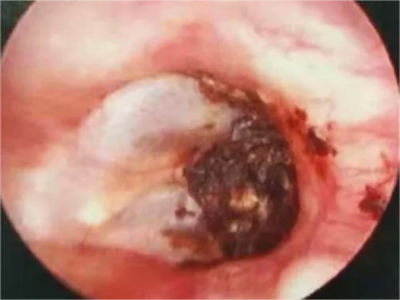

外耳道耵聍栓塞耳内黄褐色块状物图

外耳道耵聍栓塞患者外耳道分泌出黏性物质,不断堆积后形成黄褐色块状物,局部受到刺激后有出血症状,硬块表面呈鲜红色,伴有不同程度的疼痛。